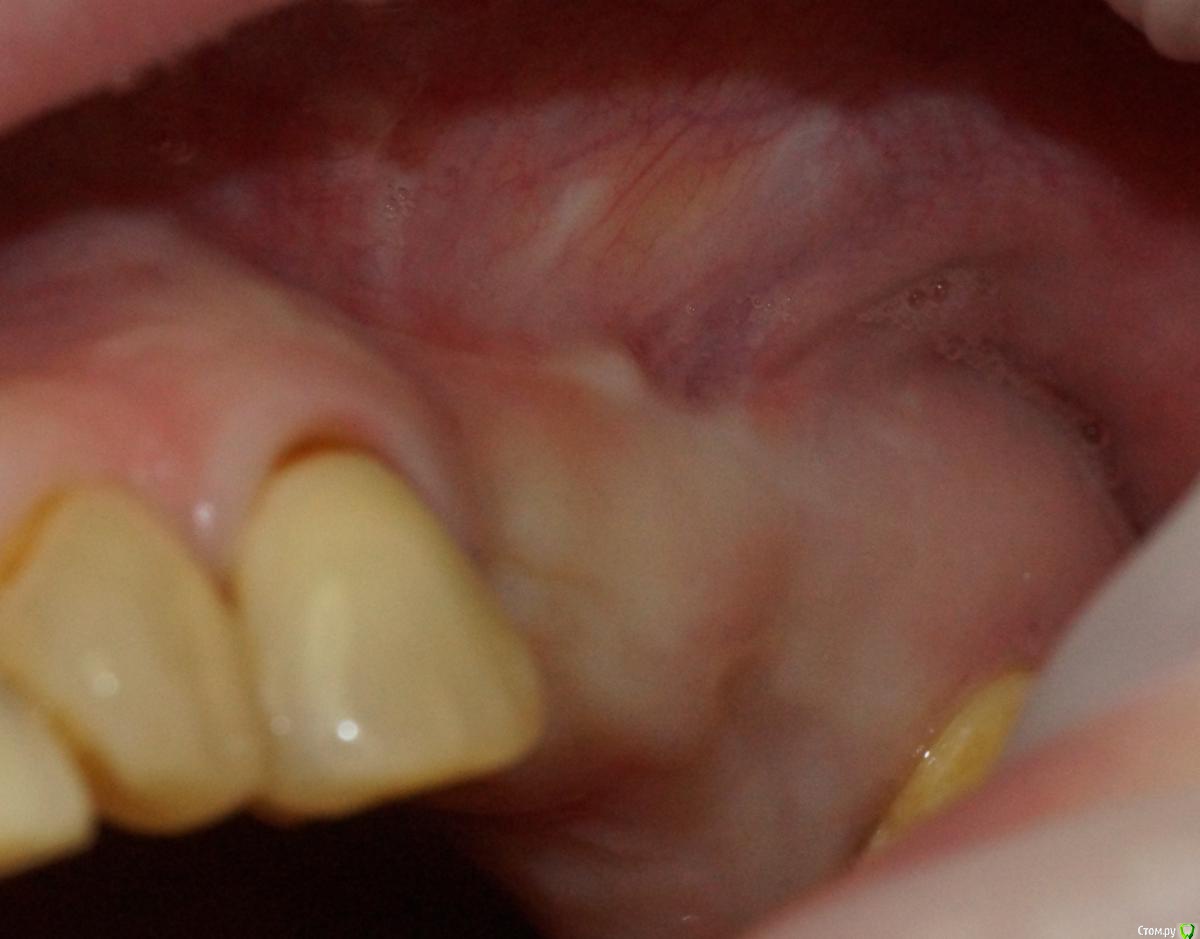

togrul Опубликовано 6 апреля, 2017 Поделиться Опубликовано 6 апреля, 2017 (изменено) Добрый день коллеги . Необходима Ваша помощь в планировании лечения. Пациентке нужно установить 2 имплантата в позиции 24-26. При анализе кт пришёл к выводу : 1 - провести НКР для восстановления высоты сеткой , через 6 месяцев установка имплантатов . 2- в области 27 зуба есть радикулярная киста , как вы считаете ее нужно убирать или нет и радикулярная ли данная киста? 3 - нужно ли проводить синус с нкр или лучше провести после НКР закрытый синус ? Буду благодарен за ответы.IMG_3292.BMPIMG_3293.BMPIMG_3294.BMP Изменено 6 апреля, 2017 пользователем togrul Ссылка на комментарий

togrul Опубликовано 6 апреля, 2017 Автор Поделиться Опубликовано 6 апреля, 2017 Спасибо за комментарий. Просматривая кт зуб 27 не вовлечен в полость кисты. Я завтра скину срезы другии, Но слизистая шнайдеровой мембраны сращена на мой взгляд с кистой . И еще один момент это рубец на границе неподвижной слизистой к подвижной. Ссылка на комментарий

togrul Опубликовано 29 августа, 2017 Автор Поделиться Опубликовано 29 августа, 2017 (изменено) Убрал содержимое кисты , получил мутное содержимое +убрал эпителий . Было сообщение полости с синусом . Ждал 3 месяца . Вот результат. Изменено 29 августа, 2017 пользователем togrul Ссылка на комментарий